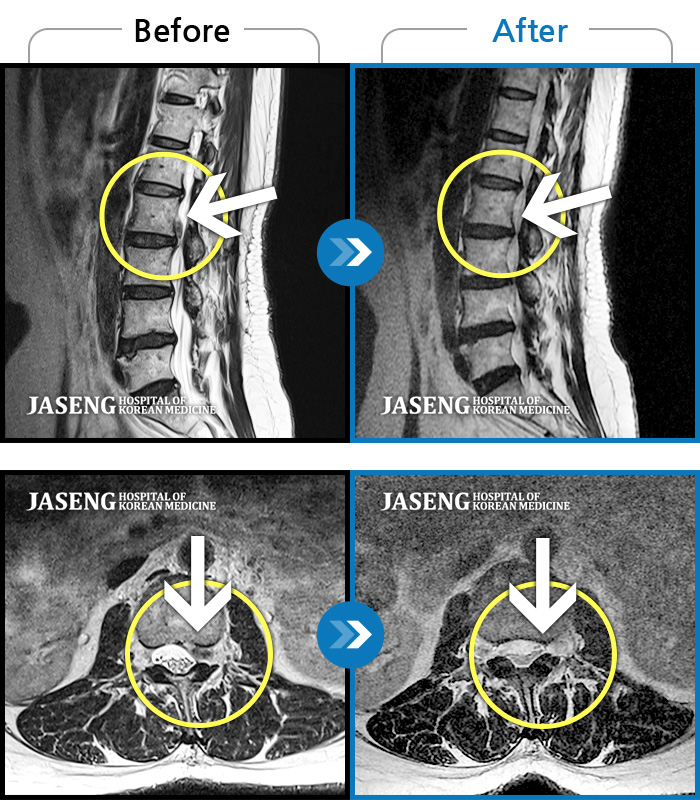

허리통증이 심해서 숙이기 어렵고 차에서 내리기 힘들었습니다.

2021.01.06 ~ 2025.03.10